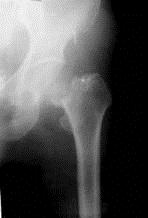

病历摘要: 患者××,女性,70岁,不慎跌倒致伤左髋部后疼痛、活动障碍2天。查体:左下肢呈屈髋屈膝及外旋畸形,右下肢活动时左髋部疼痛,左足跟和大粗隆有叩击...

问题 病历摘要: 患者××,女性,70岁,不慎跌倒致伤左髋部后疼痛、活动障碍2天。查体:左下肢呈屈髋屈膝及外旋畸形,右下肢活动时左髋部疼痛,左足跟和大粗隆有叩击痛。 为了预防人工关节术后脱位,以下措施哪些是对的?

选项 A、对髋关节周围的增生骨质和髋臼缘、股骨上段残余的骨粘固剂,术中尽可能清除,尤其是髋臼前面以及髋臼下缘、股骨小粗隆处更应清除彻底 B、术后患肢保持外展中立位,避免过早内收屈曲 C、无论何种手术途径,必须强调对软组织处理的重要性,术中软组织剥离要适当,少切除软组织,争取缝合关节周围的软组织 D、选用合适的人工关节,保持有效头颈长度,使髋关节的外展肌、内收肌处于平衡状态,以利于维持髋关节的稳定性。对髋关节曾做过手术或髋关节周围软组织较松驰的患者,以选用长颈型人工股骨头为宜 E、正确的掌握角度,将人工关节放置在合适的位置上,是预防术后脱位的关键